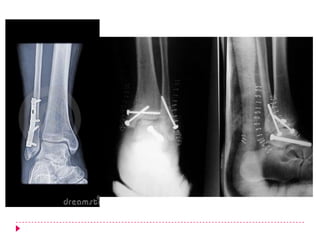

Tratamiento quirúrgico

   Indicaciones quirúrgicas:

   Fracaso de la reducción cerrada

   Fracturas desplazadas

   Fracturas inestables

   Diastasis* tibioperoneal

   Fracturas maleolares internas desplazadas

   Fracturas abiertas

   Todas las lesiones tipo A deberán ser manejadas

quirúrgicamente. El tratamiento quirúrgico

comprende la osteosíntesis estable con placas de

tercio de caña más tornillos de cortical de 3.5 y

esponjosa 4.0 en diferentes longitudes, de acuerdo

a medidas preoperatorios.

   Fracturas bimaleolares

   Estas fracturas son para manejo quirúrgico. Se debe realizar reducción abierta y

fijación interna al maléolo externo al igual que al medial cuando existe fractura del

mismo.

   El desplazamiento de los fragmentos generalmente se da hacia el maléolo externo

con una inclinación en valgo del talo.

   Durante la inmovilización inicial se intentar reducir el talo a la mortaja tibioperonéa

corrigiendo el desplazamiento lateral y la inclinación en valgo del mismo. La férula

debe mantener esta posición lo cual puede lograrse llevando el tobillo a una

posición de varo (o inversión. De esta manera debe remitirse al paciente a un

centro en el cual se le pueda dar un manejo quirúrgico al paciente.